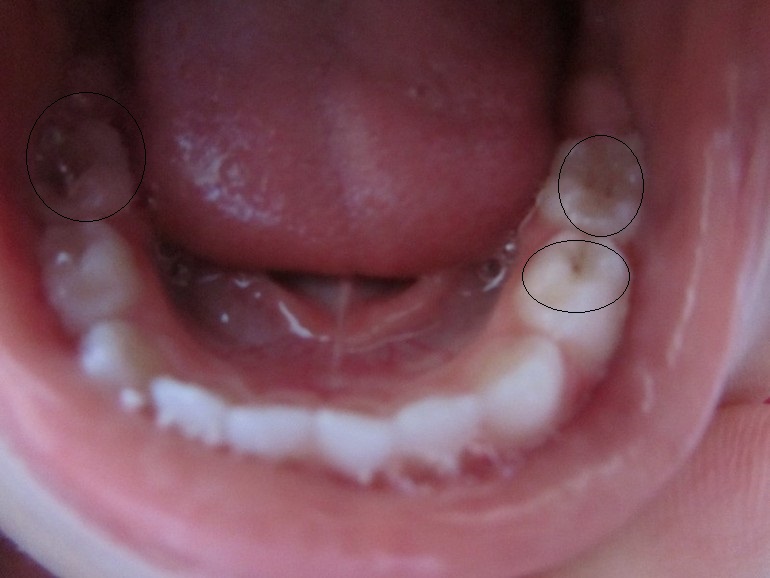

Скажите пожалуйста что можно/нужно делать с нашим вторым правым зубом? Серебрение я совсем не хочу применять, может что то другое типа Айкона?

И сегодня когда фотографировала увидела что на втором левом тоже начинает появляться белое пятнышко такое же как на левом. Что делать с ним?

И еще, на жевательном нижнем левом зубе (честно, не знаю как он называется) мне кажется или там маленькая коричневая точечка это тоже кариес? Может нужно полечить пока он совсем маленький?